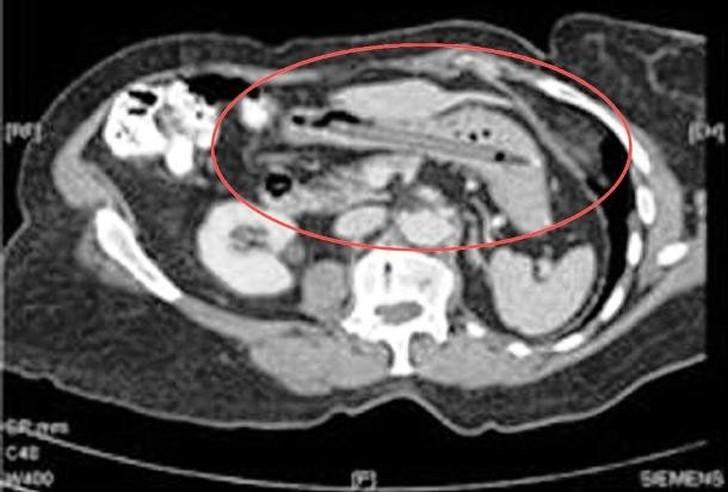

18. Зародыш близнеца.